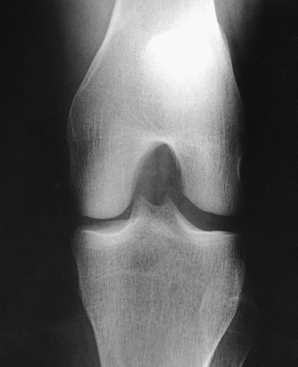

Leach et al.1 recommended that a bilateral weight-bearing AP projection be routinely included in radiographic examination of arthritic knees. They found that a weight-bearing study often reveals narrowing of a joint space that appears normal on a non–weight-bearing study.

Structures shown: The resulting image shows the joint spaces of the knees. Varus and valgus deformities can also be evaluated with this procedure (Fig. 6-128).

Structures shown: The PA weight-bearing method is useful for evaluating joint space narrowing and showing articular cartilage disease (Fig. 6-130). The image is similar to images obtained when radiographing the intercondylar fossa.